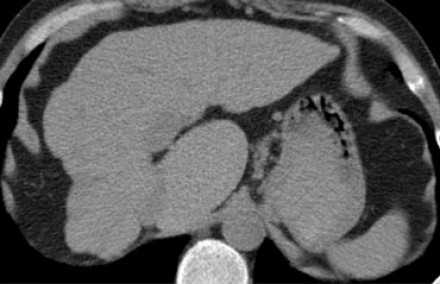

Хвостатая доля.

![10]()

Расположена сзади. Анатомическое отличие заключается ее в том, что венозный отток из доли идет чаще отдельно непосредственно в нижнюю полую вену. Также к доле кровь поставляется как от правой, так и от левой ветви воротной вены.

Этот КТ пациента с циррозом печени с атрофией правой доли, с нормальным объемом левой доли и компенсаторной гипертрофией хвостатой доле. Изображение представлено ниже.Немного о хирургии печени